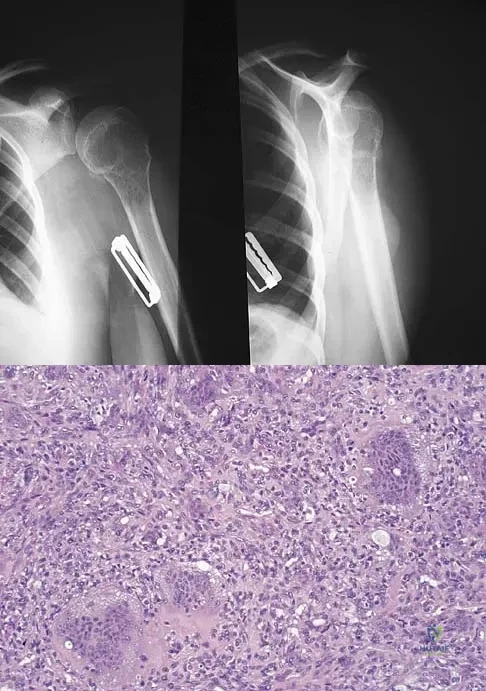

A 25-year-old woman has significant pain and swelling in her left ankle after falling off her bicycle. Examination reveals that she is neurovascularly intact. Radiographs are shown in Figures 33a through 33c. What is the next most appropriate step in management?

Explanation

Figures 47a through 47f show the AP radiograph, bone scan, CT scan, MRI scan, and biopsy specimens of a 30-year-old woman who has had vague left shoulder pain for 1 year. Management should consist of

Explanation

A 34-year-old woman reports constant midlateral arm pain after sustaining minimal trauma to the shoulder. Radiographs and a biopsy specimen are shown in Figures 29a and 29b. What is the most likely diagnosis?

Explanation